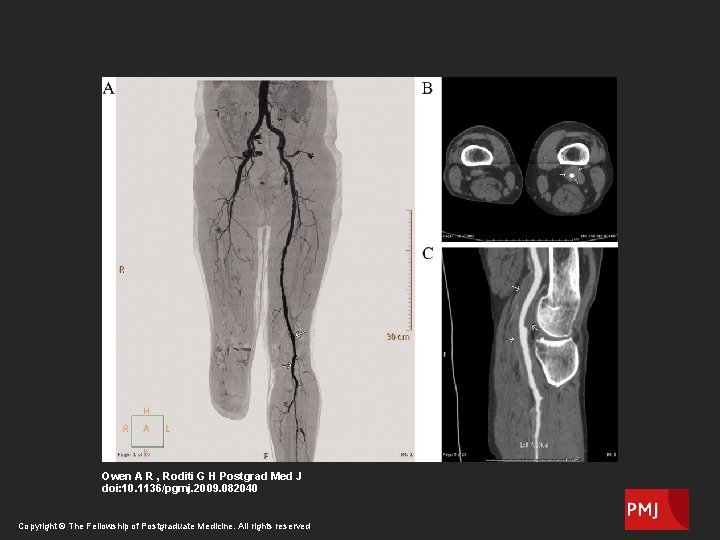

CT Angiography

Owen A R , Roditi G H Postgrad Med J doi: 10. 1136/pgmj. 2009. 082040 Copyright © The Fellowship of Postgraduate Medicine. All rights reserved.